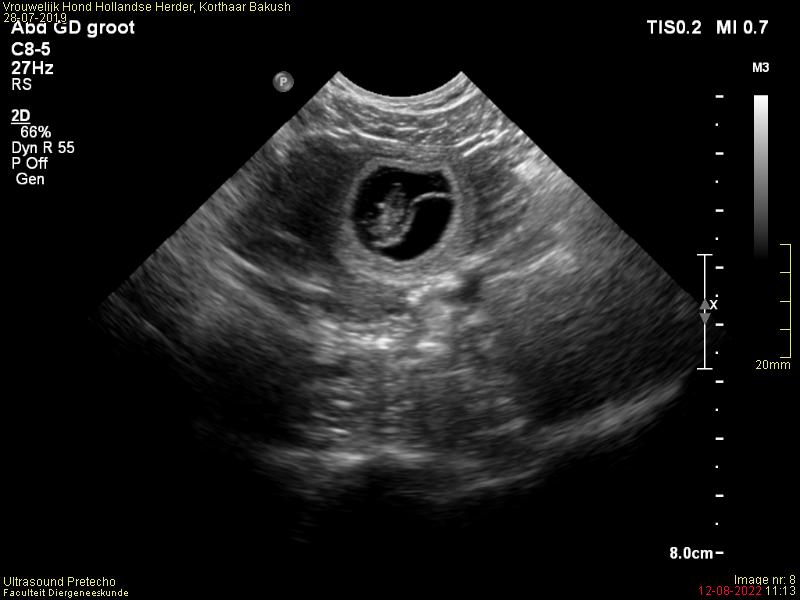

Met Bakush gaat alles heel goed. We gaan langzaam naar het einde van de dracht.

Blij, blij blij, vandaag de dracht echo gehad en Bakush is drachtig van een mooi nest.

We gaan nu afwachten op de drachtecho, welke gepland staat op 12 augustus, of de ontmoeting ook zijn vruchten heeft afgeworpen 🙂